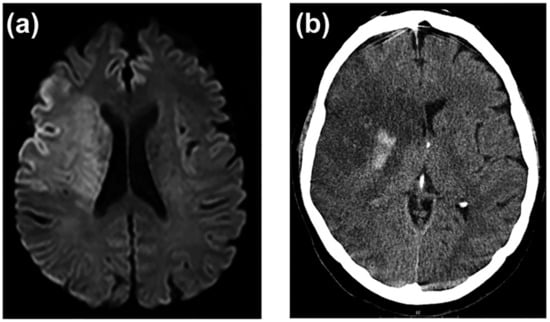

- Heiss, W.-D. Malignant MCA Infarction: Pathophysiology and Imaging for Early Diagnosis and Management Decisions. Cerebrovasc. Dis. 2016, 41, 1–7. [Google Scholar] [CrossRef] [PubMed]

- Wu, M.-N.; Fang, P.-T.; Hung, C.-H.; Hsu, C.-Y.; Chou, P.-S.; Yang, Y.-H. The Association between White Matter Changes and Development of Malignant Middle Cerebral Artery Infarction. Medicine 2021, 100, e25751. [Google Scholar] [CrossRef] [PubMed]

- Hoehn-Berlage, M.; Norris, D.G.; Kohno, K.; Mies, G.; Leibfritz, D.; Hossmann, K.A. Evolution of Regional Changes in Apparent Diffusion Coefficient during Focal Ischemia of Rat Brain: The Relationship of Quantitative Diffusion NMR Imaging to Reduction in Cerebral Blood Flow and Metabolic Disturbances. J. Cereb. Blood Flow Metab. 1995, 15, 1002–1011. [Google Scholar] [CrossRef] [PubMed]

- Von Kummer, R.; Meyding-Lamadé, U.; Forsting, M.; Rosin, L.; Rieke, K.; Hacke, W.; Sartor, K. Sensitivity and Prognostic Value of Early CT in Occlusion of the Middle Cerebral Artery Trunk. AJNR. Am. J. Neuroradiol. 1994, 15, 9–15; discussion 16–18. [Google Scholar]